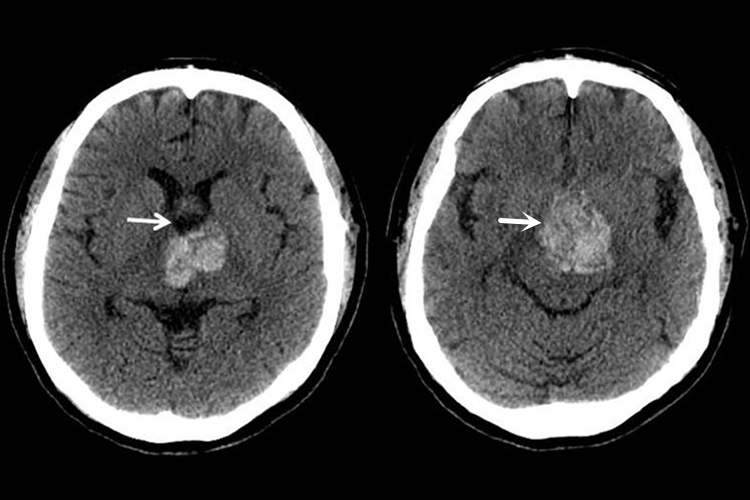

海绵状血管瘤

属于脑血管畸形,血管瘤外观为紫红色,表面呈桑葚状,剖面呈海绵状或蜂窝状,质地可软可硬。血管瘤常有分叶囊包裹,与周围分界清楚。